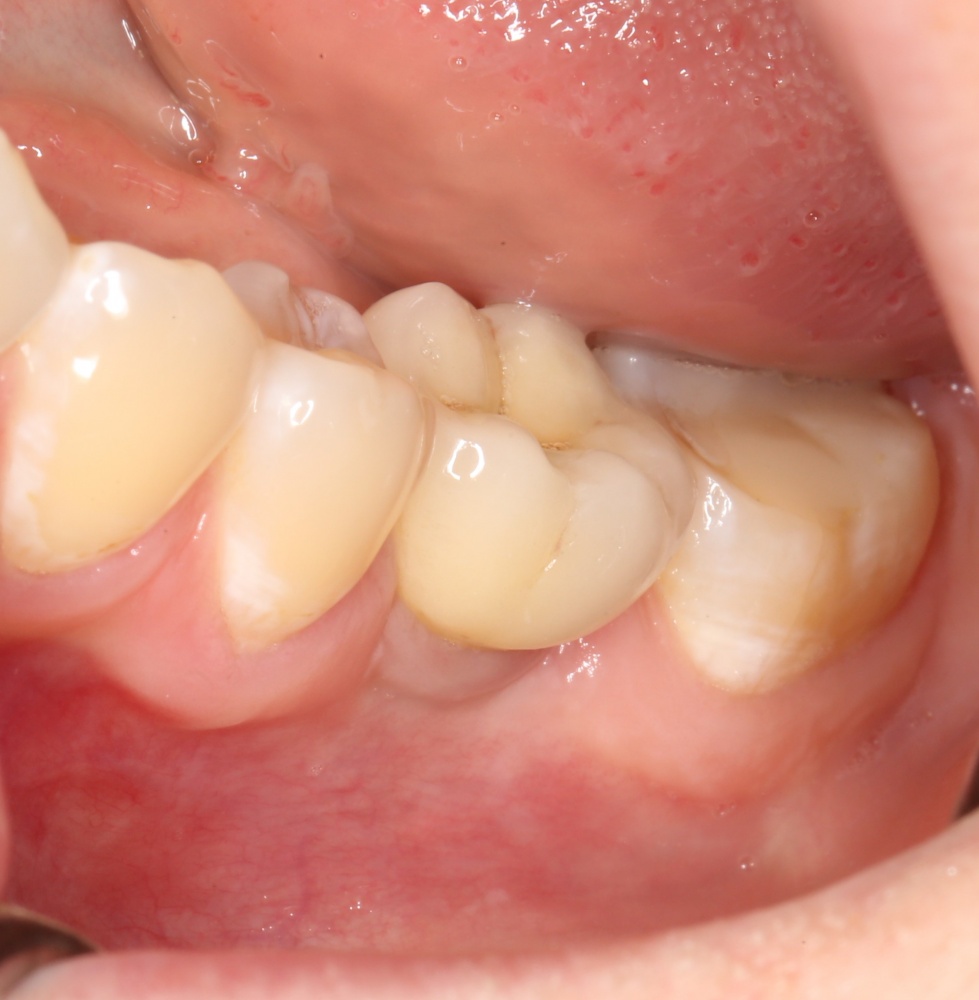

Давайте внимательно посмотрим на состояние лунок центральных резцов после удаления:

Приемлемый фенотип (сочетание толщины и ширины участка жевательной десны) — это, конечно, приятно. Но гораздо важнее сосредоточиться на рисках, их на этот момент два:

— травматическое повреждение слизистой, вызванное удаление зубов связано с тем, что при хроническом воспалении слизистая оболочка теряет эластичность, поэтому легко рвётся. Такая ситуация создаёт серьёзную угрозу эстетическому результату лечения, в зависимости от того, насколько быстро десна придёт в норму.

— как и предполагалось после КЛКТ, утрата костной стенки привела к тому, что десна провалилась в просвет лунки левого центрального резца. Это еще больше усугубляет клиническую ситуацию.

Для нас это не было неожиданностью. Зная закономерности изменений тканей при хроническом  воспалении и данные КЛКТ, мы можем довольно точно предсказывать развитие клинической ситуации и соответственно к ней подготовиться. Именно поэтому, помимо обычной немедленной имплантации, мы запланировали аугментацию лунки с помощью биоматериалов и метода трансплантации лоскута (см. предварительные планы лечения).